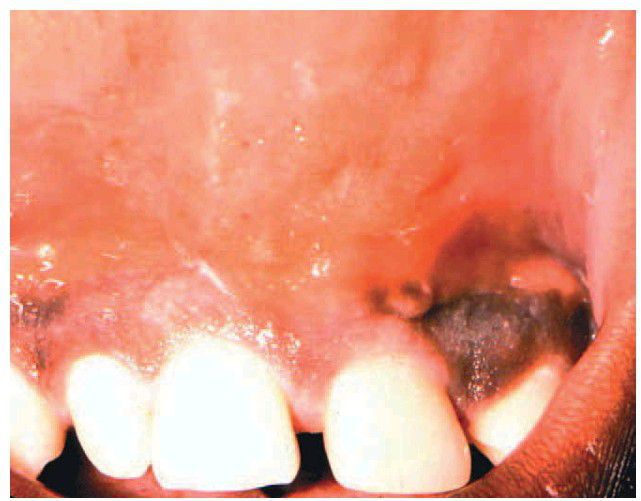

Odontogenic infection

Fluctuant swelling in mucobuccal fold associated with periradicular disease from the maxillary central incisor.